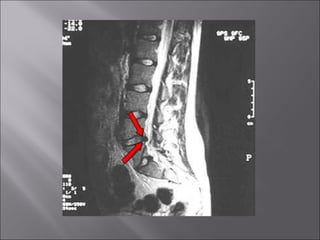

Articulaciones  de los cuerpos vertebrales Disco intervertebral Ligamentos

Inserción robusta entre un cuerpo vertebral y otro. Soporta el peso y los choques. Da la forma de las curvas de la columna. Se divide en: Anillo fibroso Núcleo pulposo

Laminas concéntricas de fibrocartílago.

Centro del disco intervertebral. Ayuda a la flexión y extensión de la columna